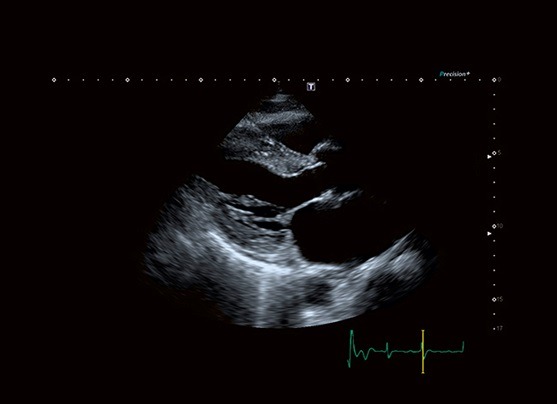

طراحی متحولانه iBeam به همراه قدرت پردازش فوق العاده افزایش یافته، شفافیت پیش بینی نشده ای را در تصویربرداری از ظریف‌ترین تا درشت‌اندام‌ترین بیماران با عمق نفوذ بهبود یافته فراهم می آورد.

Tissue Enhancement تصاویری با یکنواختی و وضوح حیرت انگیز و نمایش بهبود یافته ای از مرزهای قلبی، بالاخص برای بیماران با شرایط سخت، ارائه می‌دهد.